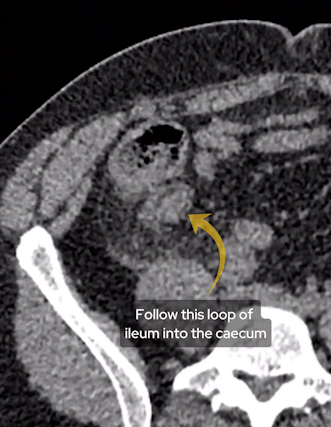

When you suspect a right iliac fossa (RIF) abnormality, first start by identifying the caecum. I do this by tracing the colon all the way from the rectum back to the origin. Once you find this, in normal circumstances you will find two things communicating with it. Firstly the terminal ileum and then the appendix.

You should be able to recognise the terminal ileum as communicating with the rest of the small bowel but also look out for some fat density which you will normally find with a normal ileocaecal valve as we can see below.

Find the terminal ileum by identifying the distal small bowel and finding the ileocaecal valve.

Separate to the terminal ileum we can see a second structure communicating with the caecum – this is a dilated appendix.